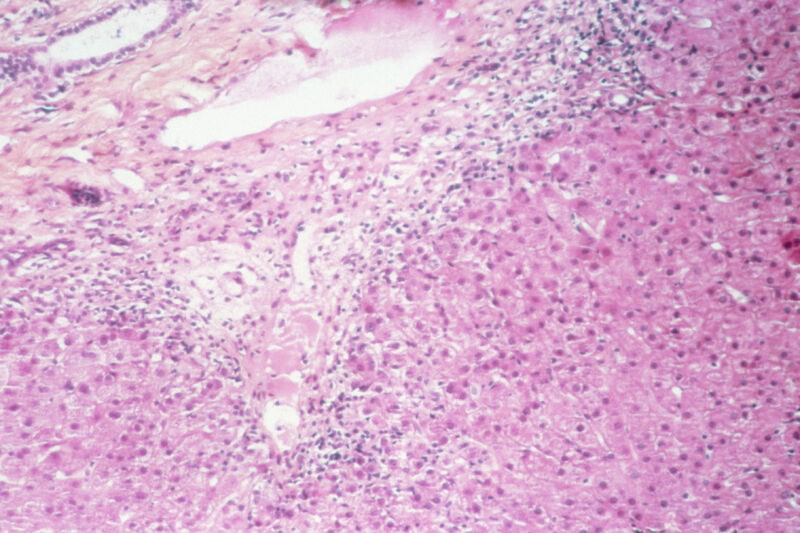

Enlarge / Liver lesions in patient with chronic active hepatitis C. (credit: Getty | BSIP)